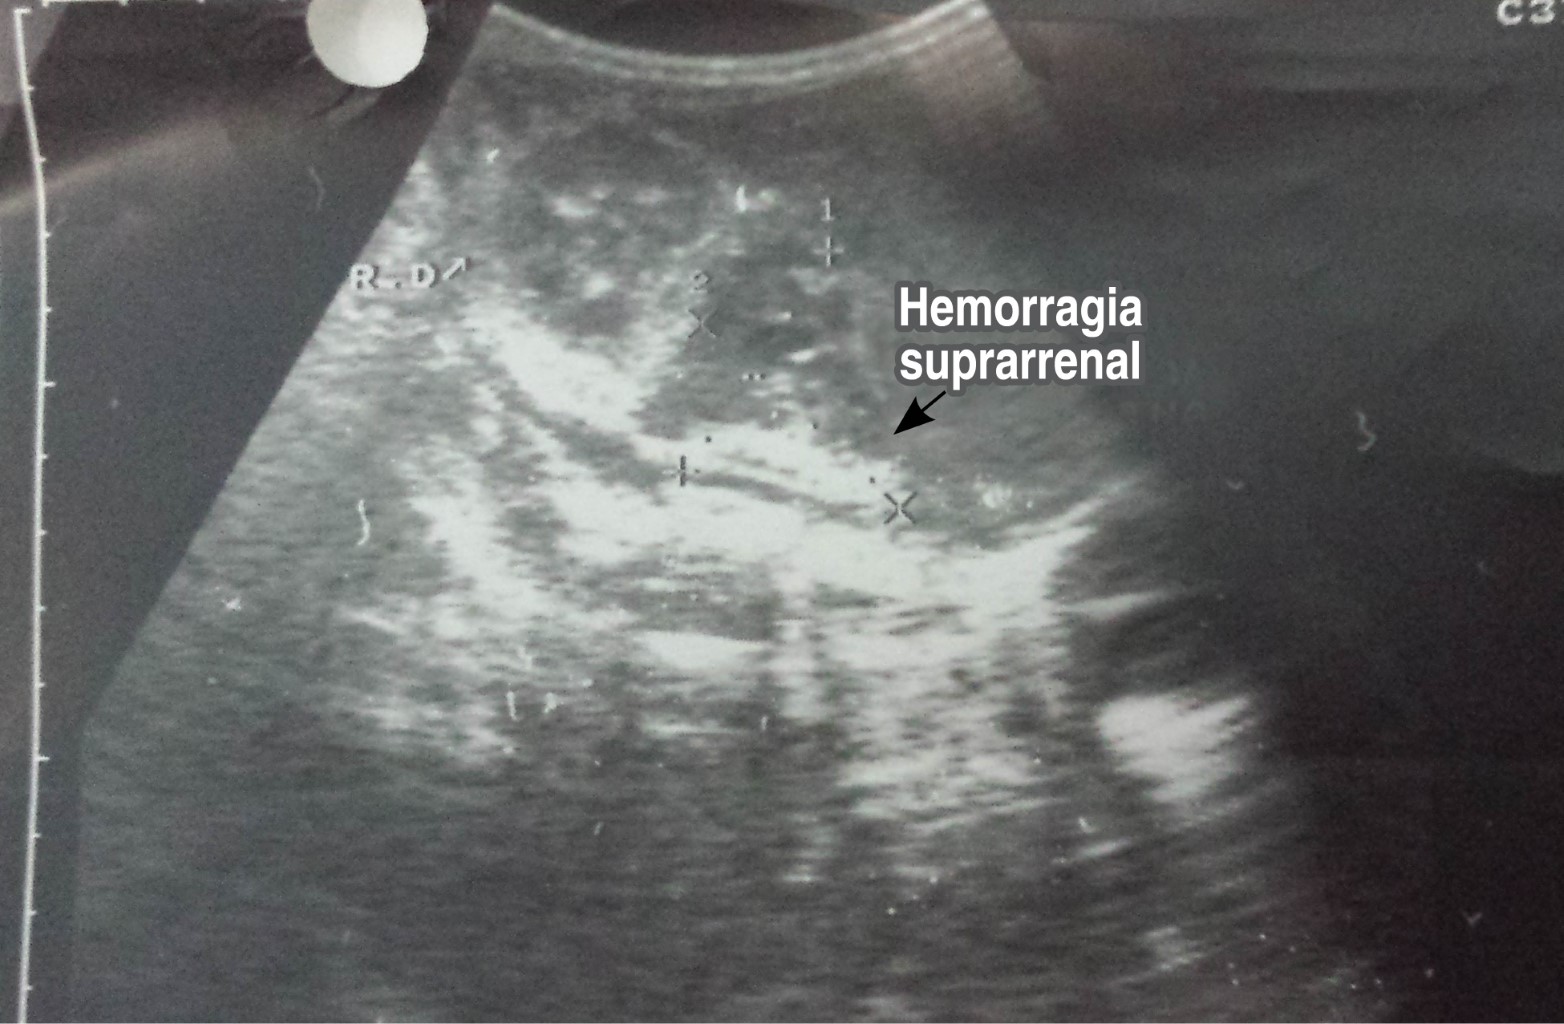

Se decide transfusión de paquete globular, así como transfusión con plasma y aporte de vitamina K. El seguimiento ecográfico de abdomen se realizó cada tres días, observando reabsorción completa de la hemorragia (Figura 2). El RN fue egresado a los 16 días de edad sin complicaciones.

Figura 2